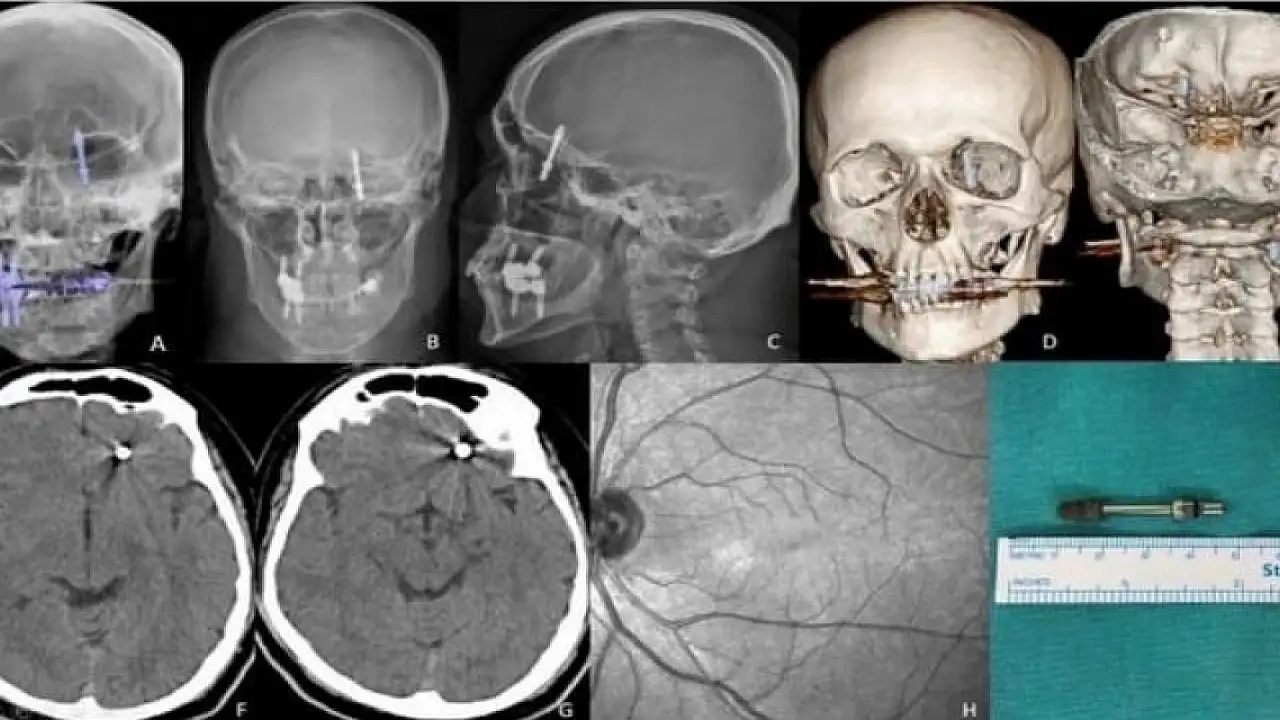

Bursa'da bir vatandaşın sızı yapan dişlerinin tedavisi için gittiği özel bir klinikte implant tedavisi başlatıldı. Doktor çeneye yerleştirecek vidayı zorlayınca vida çene kemiğini delip hastanın beynine saplandı. Hastaneye kaldırılan vatandaş saatler süren ameliyat sonrası hayata tekrar döndü.

İddiaya göre, implantı çeneye yerleştirmek isteyen doktorun yanlış müdahalesi sonrası vida, Yılmaz'ın çene kemiğini delip kafatasına saplandı. Acı içinde kalan Yılmaz'ın yaşadığı baygınlık sonrası film çeken Doktor A.D., vidanın kafatasında olduğunu görünce hemen kendi aracıyla Yılmaz'ı bir hastaneye bıraktı. Hastanede çekilen tomografi sonrası gözlerine inanamayan doktorlar, 2 çocuk babası adamı hemen ameliyata aldılar. Saatlerce süren operasyon sonrası hayata tekrar dönen Yılmaz, günlerce taburcu olmayı bekledi. Sağlığına dönen Yılmaz, kendisine yanlış müdahale yapan diş hekimini aradığında ise ikinci bir şoku yaşadı. Yaptığı ödemenin iadesini isteyen Yılmaz'a doktor tarafından ret cevabı gelince Yılmaz, yargının yolunu tuttu.

Kendisini uyarmasına rağmen dinlemediğini ifade eden Yılmaz, "Daha sonra dişlerimi çekip, aynı gün implant uygulaması yaparken, işlemde kullandığı cihazın bozuk olduğunu sekreterine söyledi. Bu kez de işlemi eliyle yapmaya başladı. Vidayı yerleştirmeye çalışırken, aşırı yüklendiğini fark ettim. Bunu kendisine söyledim, kemik sesi geldiğini ifade ettim. Fakat bu kez de bana bunun normal olduğunu söyledi. Ama vidayı zorlarken, vida çene kemiğimi delip göz duvarının arkasından beyin omurilik sıvısının olduğu bölgeye saplandı. Ben acıdan dolayı bağırınca röntgen çektirdi" dedi.

Doktorun kendisini hastaneye bırakıp kaçtığını iddia eden Yılmaz, "Durumun ciddiyetini anlayınca beni Uludağ Üniversitesi Hastanesinin Acil bölümüne getirip gitti. Burada yapılan inceleme sonrası vidanın beyin omurilik sıvısının olduğu yere saplandığı görüldü. Daha sonra uzman hekimler bir araya gelip, ameliyat için karar aldılar. Ameliyat öncesi bana hayatımı kaybedebileceğimi söylediler. Ben artık çocuklarımla helalleşip vedalaştım. Çok şükür ameliyattan sağ salim çıktım. Bu süreçlerde diş hekimi hiç bir zaman yanımda olup mağduriyetimi gidermedi, hatta ödediğim ücreti dahi geri iade etmedi. Üstüne üstelik benimle dalga geçer gibi konuştu. Bunların hepsi belgeli. Ben yetkililerden devlet büyüklerimizden bu konuyla ilgilenilmesini istiyorum. Benim iki çocuğum var. Bana bir şey olsaydı bunların hesabını kim verecekti ? Şimdi dava sürecine girdik. Kendisinden şikayetçi oldum" diye konuştu.

Öte yandan Yılmaz'ı sağlığına kavuşturan doktorların başarılı ameliyatı, Amerika'da literatüre girip dergilere konu oldu.